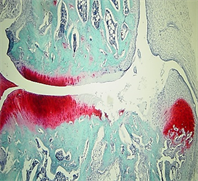

A new method for measuring bone marrow lesions for pain research in people with osteoarthritis

Within the bones of people with osteoarthritis there are often regions called Bone Marrow Lesions (BMLs) which are seen using MRI scanners. They appear to be linked to inflammation and pain. When BMLs are close to the knee joint, they appear to be closely related to osteoarthritis knee pain. Joint tissues are very useful for research aiming to characterise cells and molecules that might be targeted by new drugs in order to relieve pain.

For more details, visit the summary page